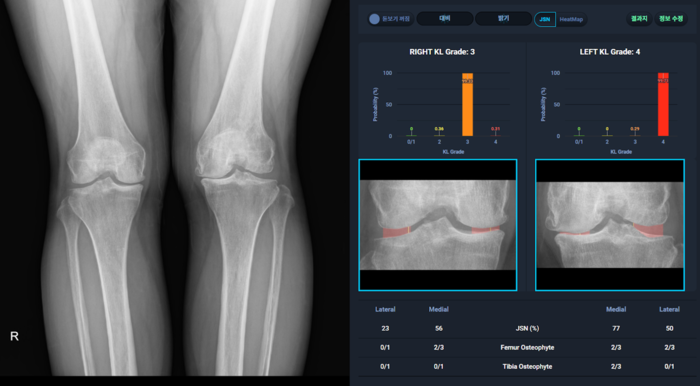

Crescom社の代表的なソリューションは、△TW3(Tanner-Whitehouse3)·GP(Greulich Pyle)ハイブリッド方式の骨年齢分析ソリューションMediAI-BA △健康保険審査評価院で全数検査に適用している、定量的膝関節炎の深刻度自動分析ソリューションMediAI-OA △世界最初で一般の放射線画像から舟状骨(Scaphoid)の検出が出来る人工知能手首骨折検出ソリューション MediAI-FXなどがある。